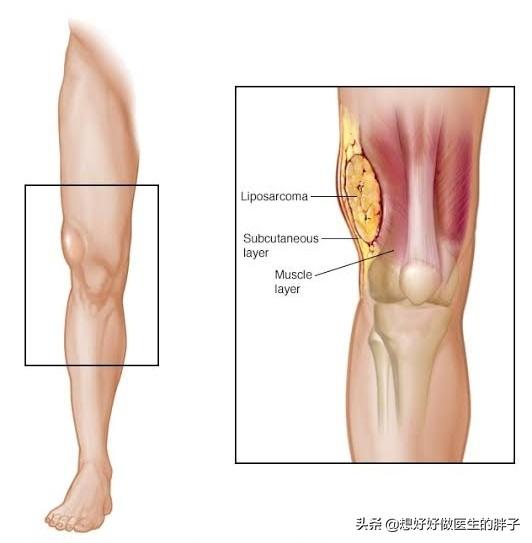

这个问题其实是一直存在争议的,大部分的学者认为脂肪瘤是一种良性肿瘤不会恶变。然而在临床上也确实存在着一种疾病,称之为脂肪肉瘤。也在学界被拿出来,证明脂肪瘤是可以恶变的。

但是后来经过论证认为脂肪肉瘤在疾病的症状和表现上与脂肪瘤类似,也就是说当患者和医生发现肿物的时候,并不能明确的知道肿物是脂肪瘤还是脂肪肉瘤,就像我们看到了两个鸡蛋在皮儿上都是一样的,但是一个是好鸡蛋,一个是臭鸡蛋,如果不将壳打开,我们根本就不能明确鸡蛋的好坏。脂肪瘤的问题上也是这样,我们在体表上都能看到是一个肿物,两者并不存在明显的区别,只有将其手术切除,做病理才能明确是否为恶性肿瘤。也并不能证明脂肪肉瘤是脂肪瘤转化而来的【6】。

目前认为如果肿物部位出现疼痛、不适以及肿物超过5厘米时建议要进行病理检查排除脂肪肉瘤可能性,可以切除部分肿物的被膜或者完整切除肿物后进行病理学检查,明确是否是脂肪肉瘤。